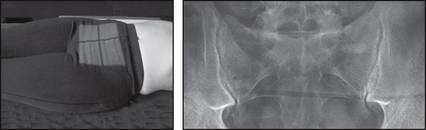

SACRUM

image

Projection: AP

Centring Point: Midline 5 cm above superior border of symphysis pubis. Cranial – central ray: 10° male, 20° female

Projection: LATERAL

Centring Point: Midway between the PSIS and the palpable coccyx

Points to consider

Technique

image AP – lower bowel preparation is an advantage

image AP – central ray will differ between males and females

image Lateral – where indicated place a non-opaque pad under the waist

Page 121

Radiological assessment

image Must demonstrate the sacrum and sacroiliac joints

image Obturator foramina will appear wide open

image Symphysis will appear broadened depending upon tube angle

image Lateral – must include the L5–S1 joint space on the radiograph

AP

Patient supine

Median sagittal plane perpendicular to the table top and ASIS equidistant

Hips and knees are flexed and may be supported in position

Collimation

To include: SUPERIORLY: L5–S1 joint space

INFERIORLY: Coccyx

LATERALLY: Sacroiliac joints

Lateral

Patient lies on their side

Median sagittal plane parallel to the table top

Hips and knees are flexed

PSIS are perpendicular to the table top

ANTERIORLY: Sacral promontory and coccyx

POSTERIORLY: Sacral spinous tubercles